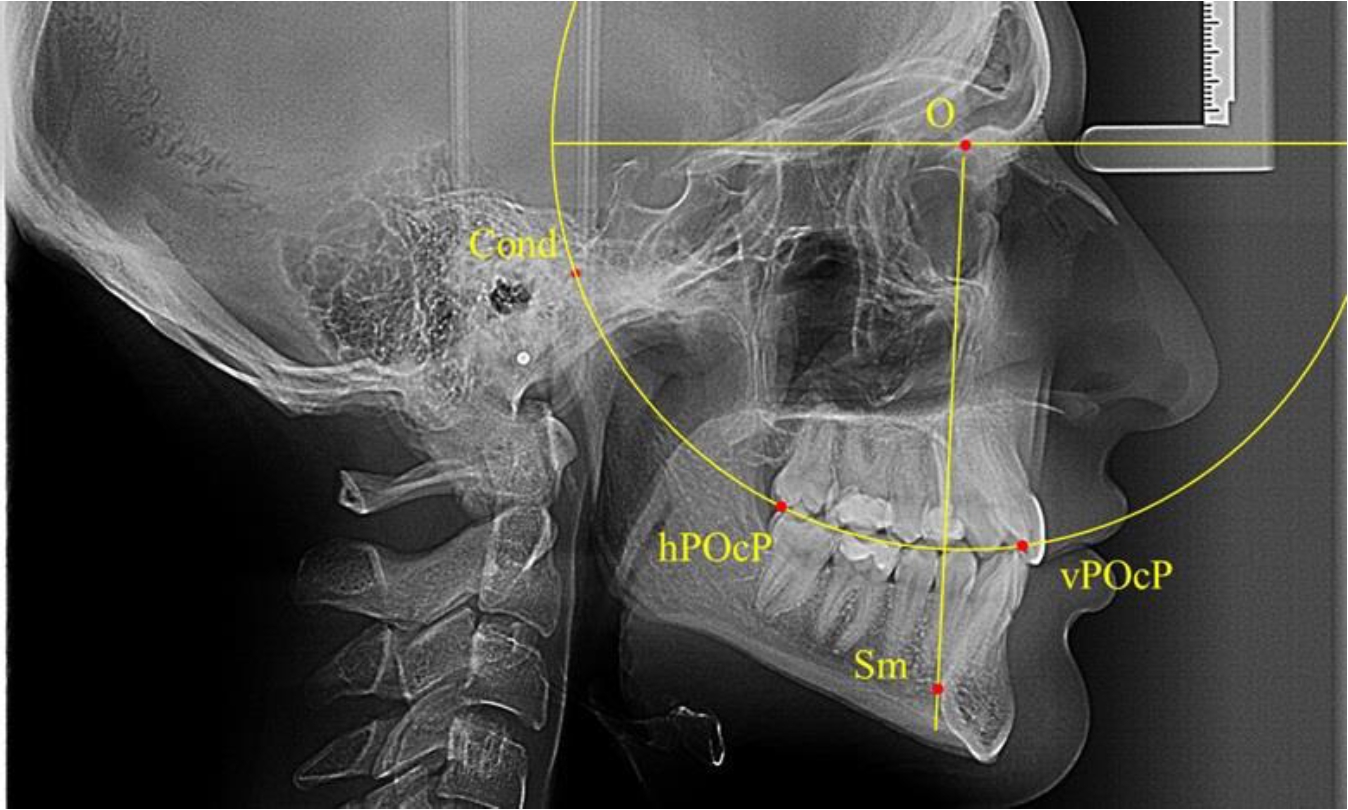

Анализ снимков проводили с использованием традиционного построения стресс-оси по Bimler. Для удобства построения использовали компьютерную программу PowerPoint. Основными точками для построения круга были передняя (vPOcP) и дистальная (hPOcP) окклюзионные точки, а также верхняя выпуклость суставной головки (Cond).

Вставка из программы в виде овала накладывалась на фотографию рентгенограммы и ручным способом растягивалась так, чтобы получился круг, проходящий через обозначенные реперные точки.

Центр окружности О, соединяющей точку резцового перекрытия с жевательной поверхностью зубов и серединой суставных головок, соединяли с выступающей точкой Sm на внутреннем контуре подбородка (рис. 1).

Рис. 1. Метод анализа ТРГ по Bimler

В норме, по резульатам исследования автора, линия Bimler проходила по вертикальной оси первых премоляров, что мы также расценивали как оптимальное их расположение.

В группе рентгенограмм, выделенных по признаку протрузионного положения резцов, также проводилось распределение на подгруппы с учетом широтных размеров подбородочного выступа.

Анализ результатов показал, что практически при всех вариантах подбородочного выступа в данной группе исследования первые премоляры, как правило, располагались впереди стресс-оси Bimler. Рентгенограммы пациентов с протрузионным положением резцов при среднем и узком варианте подбородочного выступа представлены на рис. 3.

Таким образом, для людей с протрузионным типом зубочелюстных дуг характерно расположение первых премоляров впереди стресс-оси, и этот показатель не может быть использован в качестве выбора метода лечения аномалий для данной группы исследования вне зависимости от формы подбородочного выступа.

Рис. 3. Положение первых верхних премоляров при протрузии со средними (а) и узкими (б) размерами подбородка